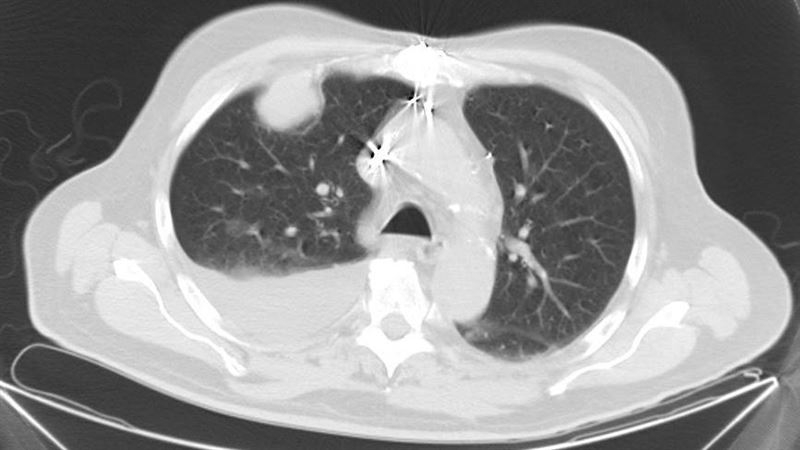

【致癌習慣/二手石棉/建築工人/肺癌/石棉暴露】美國57歲女子Heather Von St James擁有一個特別的患癌經歷。她在36歲、懷有第一胎時發現肺部有腫瘤,致癌令人意想不到,原來是源自自小很喜歡穿父親從建築工地帶回家的一件外套。她父親長期在工地工作,外套上早已沾滿了微小的石棉微粒。每當她穿上外套,這些肉眼看不見的纖維就會飄散,不知不覺被她吸入肺部,為日後的健康埋下了致命危機。

美國女子Heather在36歲懷第一胎期間,開始出現持續發燒、極度疲倦及胸口強烈壓迫感。起初她以為只是產後不適,但檢查後發現肺部有腫瘤,確診為惡性肋膜間皮瘤。這種癌症侵襲性極高,醫生當時警告,若不接受治療,她可能只剩15個月壽命。原來是因為自小穿著父親在建築工地穿著的外套、沾滿微量的石棉所致,日子久了,Heather長期在石棉暴露下患癌。

手術切左肺、化療放療 生活質量大減

Heather接受了大規模手術,切除左肺、部分肋骨及受影響的胸膜,並配合多輪化療及放射治療。雖然最終成功控制病情,但她餘生只能靠單肺生活。她坦言: